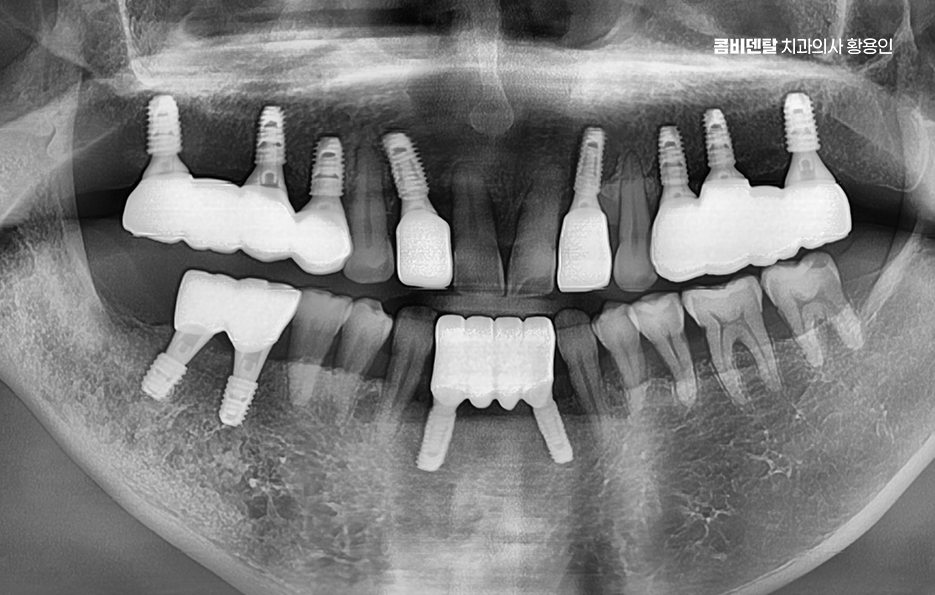

이런 상태를 “부분 무치악”이라고 부르는데 이러한 상태에서 50대임플란트 치료 계획을 세운다는 것은 전체 치열과 기능까지 다시 설계해야 하는 복잡한 치료가 될 수 있어서 50대에 여러 치아를 잃은 경우엔 임플란트 치료 계획이 단순한 ‘치아 대체’ 수준이 아니라, 전체적인 구강 재건이라는 개념으로 접근해야 할 수 있어요

50대임플란트 치료는 시작 전에 정밀한 진단이 선행되어야 하는데 단순히 빈자리만 보고 이 자리에 임플란트를 하나씩 심는 방식이 아니라 턱뼈 상태, 잇몸 높이, 씹는 힘의 분포, 전체 교합의 불균형까지 전부 고려해야 안정적이고 오래 가는 치료가 될 수 있어요

군데군데 빠진 치아를 전부 임플란트로 하나씩 심을 수도 있지만, 꼭 그럴 필요는 없으며 예를 들어 어금니 3개가 빠졌다면 3개를 다 심지 않고, 2개만 심고 그 사이를 브릿지로 연결하는 방식도 가능한데 이러한 치료 계획은 단순히 효율성이나 경제적인 측면만 따지는 것이 아니라 각 개인의 잇몸 뼈 상태와 식립 위치, 각도 그리고 사후관리까지 종합적으로 판단해야 하기 때문에 경험 많은 치과의사와 함께 충분한 상의 후에 결정해야 하는 거예요

50대임플란트 치료가 끝났다고 해서 끝이 아니라 이 시점부터 유지 관리가 무척이나 중요하며 임플란트 수명을 좌우할 수 있는데 임플란트는 영구적인 치료가 아니고 얼마나 잘 관리하느냐에 따라 수명이 달라지는 구조이기 때문에 정기적인 검진과 스케일링을 잘 실천해야 하고 집에서는 부드러운 칫솔, 치간칫솔, 치실, 필요하면 워터픽까지 활용해서 잇몸 사이 관리에 신경 써야 하겠고 음식도 처음엔 너무 질기거나 딱딱한 건 피하고, 골고루 양쪽으로 씹는 습관을 들여야 하는 등의 관리가 곧 임플란트를 얼마나 오래 쓸 수 있느냐를 좌우할 수 있기 때문에 치과 역시도 오래 함께할 곳을 잘 따져보실 필요가 있었어요